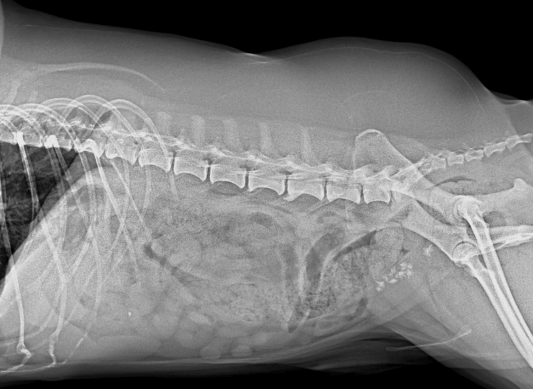

- 진단: 신체검사, 소변검사, 영상검사(방사선, 초음파 등)로 결석을 진단할 수 있습니다.